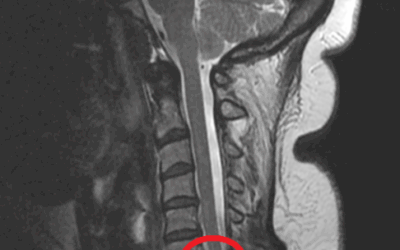

Boyunda Omurilik Kanalı Daralması (Servikal Spinal Stenoz)

Servikal Spinal Stenoz Nedir? Servikal spinal stenoz, boyun bölgesindeki omurilik kanalının daralması sonucu omuriliğe veya sinir köklerine baskı yapması durumudur. Bu baskı, sinirlerin düzgün çalışmasını engelleyerek boyun, omuz, kollar ve hatta bacaklarda...